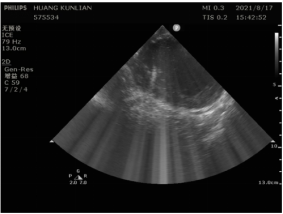

实时心包监测,为患者保驾护航

整个手术过程中,因为超声导管的存在,可以实时对心脏进行监控,观察确认病人心脏心包状态,为患者保驾护航。

图片附件

术中观察心包积液,实时监控心脏状态